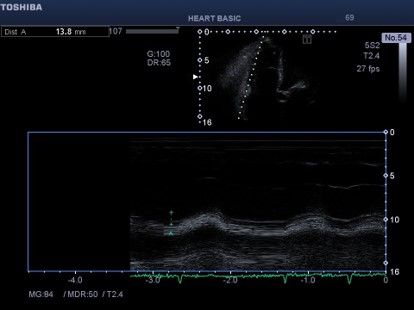

Εικόνα 4. Σημαντικά ελαττωμένη συστολική

έ κπτυξη του επιπέδου του δακτυλίου της τριγλώχινας TAPSE παρά την

σοβαρή ανεπάρκεια της βαλβίδας, εύρημα ενδεικτικό σημαντικής συστολικής δυσλειτουργίας της δεξιάς κοιλίας. Το αναμενόμενο TAPSE σε σοβαρή ανεπάρκεια τριγλώχινας είναι αυξημένο και μετρήσεις < 17 cm/s και ειδικότερα < 14 cm/s δεικνύουν δυσλειτουργία της δεξιάς κοιλίας Αντιστοίχως σε ανεπάρκεια τριγλώχινας τιμές strain ελευθέρου τοιχώματος δεξιάς κοιλίας <17% και ειδικότερα < 14% δείχνουν

δυσλειτουργία της δεξιάς κοιλίας.